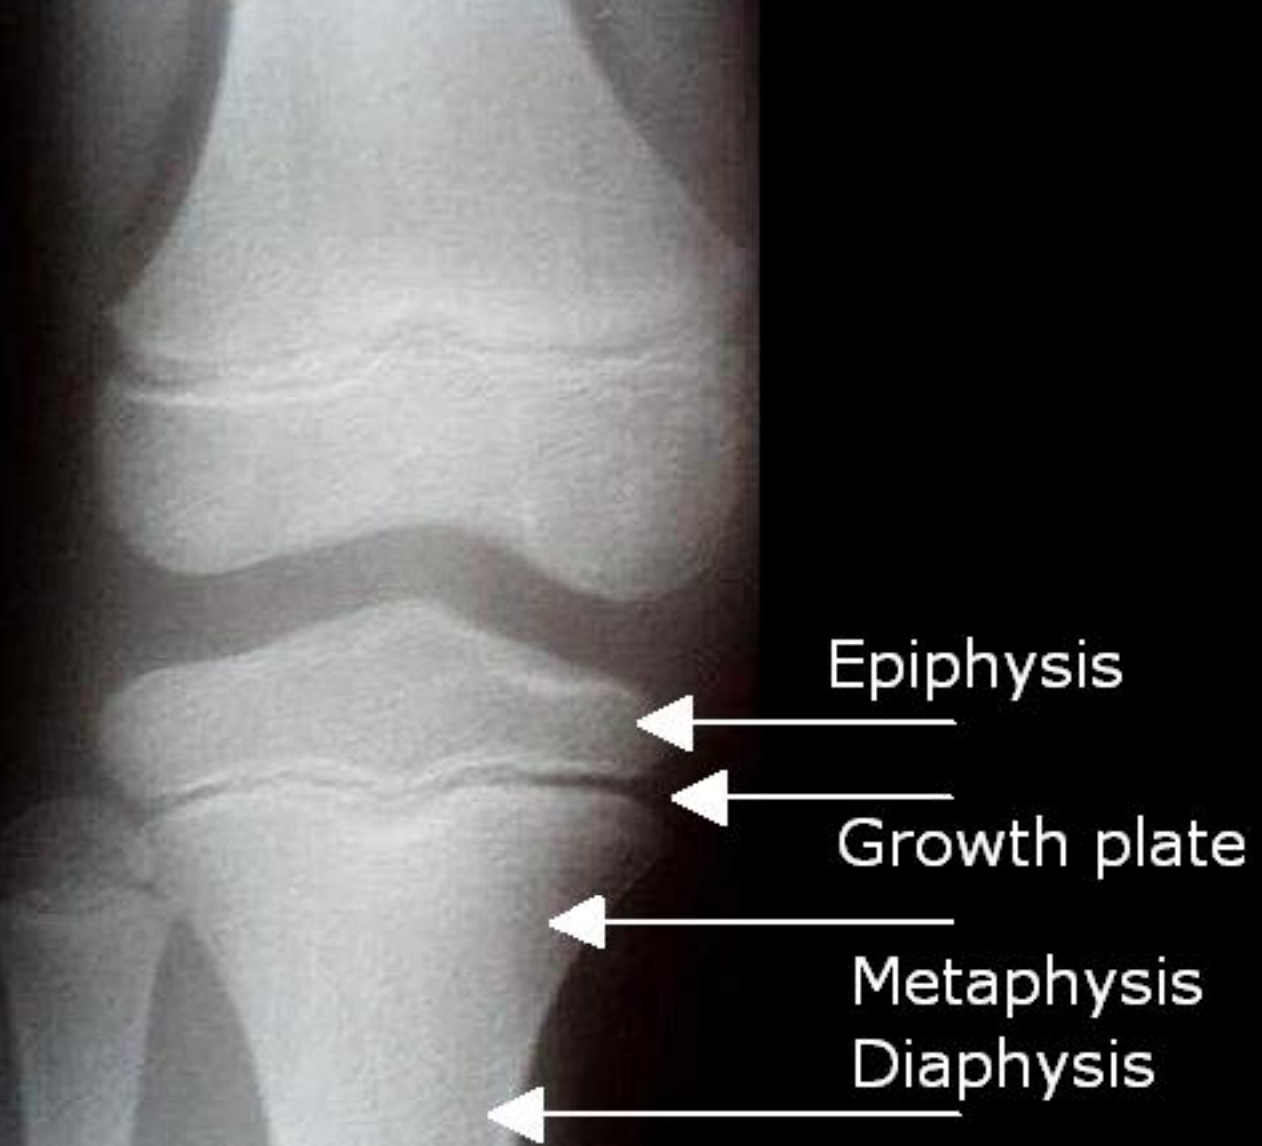

- Metaphysis artery (lat. arteriae metaphysariae)

- Branches deep in the spongiosa and nourish the area of bone and bone marrow between the diaphysis and epiphysis

- Epiphysis artery (lat. arteriae epiphysariae)

- majority arterial branches tangle of joint capsule.